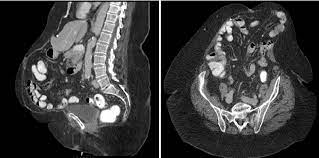

Ct Scan Sagittal View Of The Umbilical Hernia Blue Arrow Download Scientific Diagram

Ct Scan Abdomen Showing Hernia With Divarication Arrows Shows Download Scientific Diagram